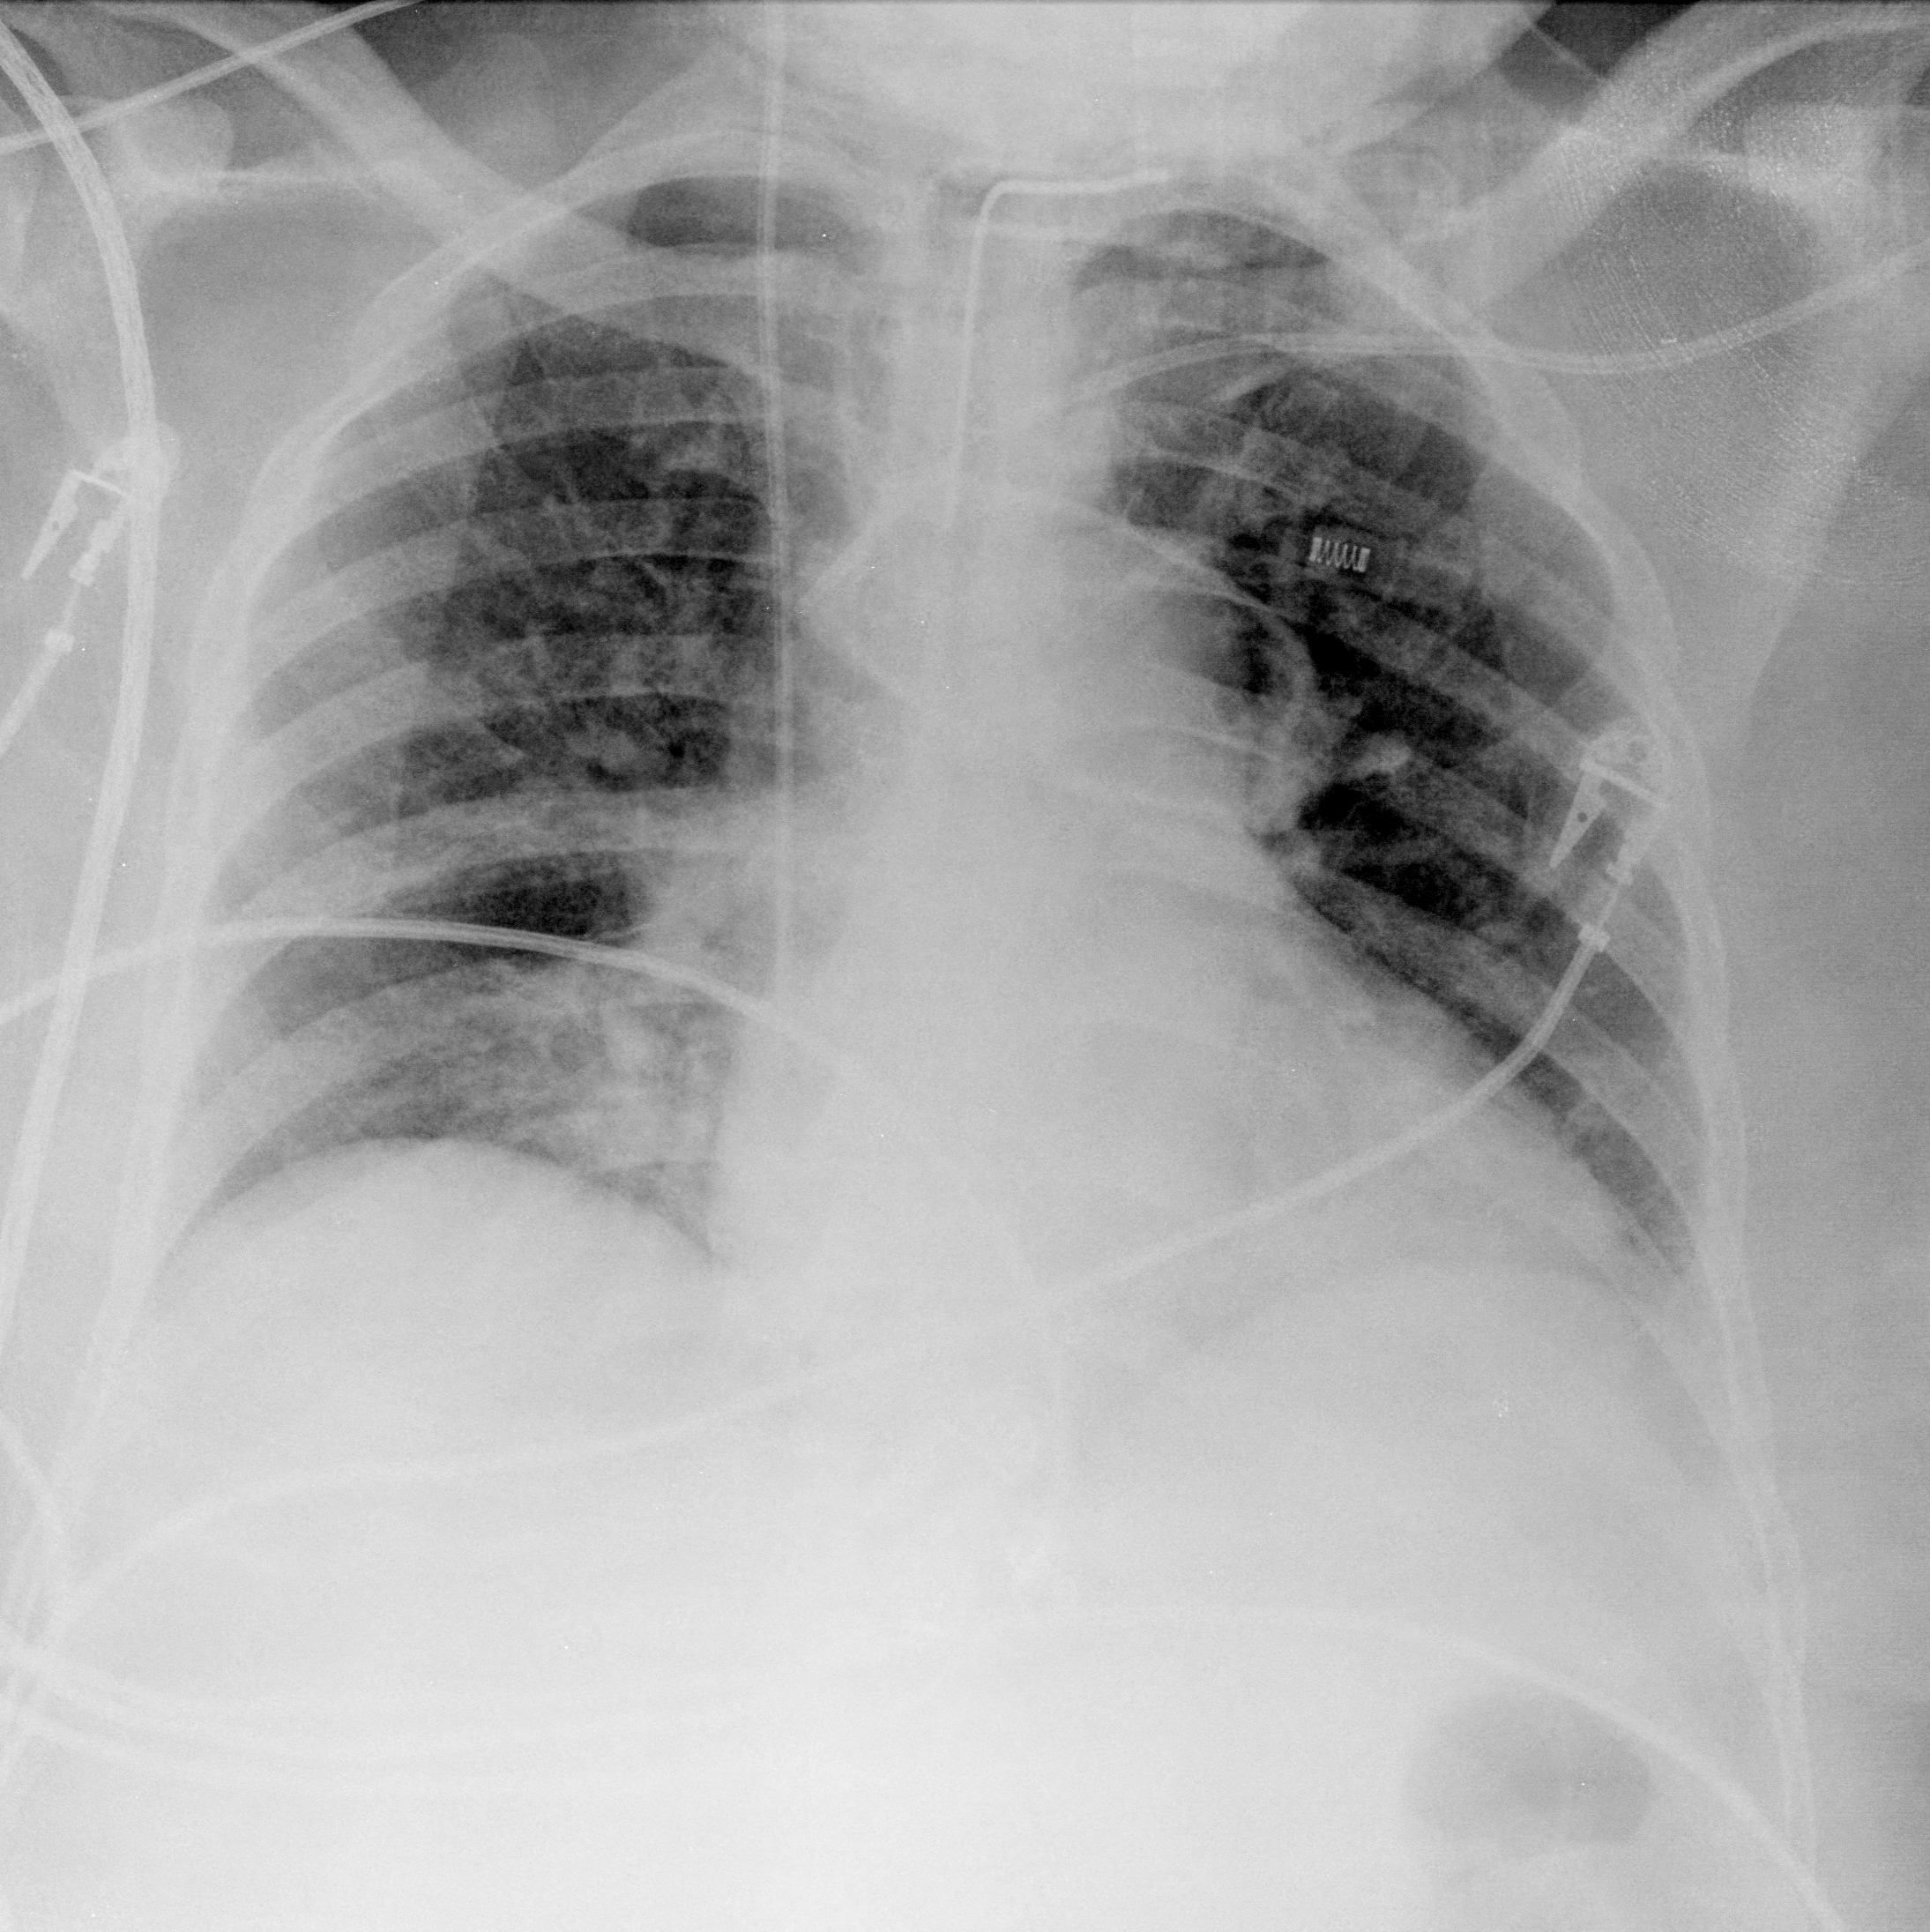

Once the SARS-COV2 reaches the host at the lung, it gets into the cells through a protein called ACE2, which serves as the ”opening” of the cell lock. After the genetic material of the virus has multiplied, the infected cell produces proteins that complement the viral structure to produce new viruses. Then, the virus destroys the infected cell, leave it and infect new cells. The destroyed cells produce radiological lesions [5, 6, 7] such as consolidations and nodules in the lungs, that are observable in the form of ground-glass opacity regions in the XR images (Fig. 1c). These lesions are more noticeable in patients assessed or more days after the onset of the disease, and especially in those older than [8]. Findings also suggest that patients recovered from COVID-19 have developed pulmonary fibrosis [9], in which the connective tissue of the lung gets inflamed. This leads to a pathological proliferation of the connective tissue between the alveoli and the surrounding blood vessels. Given the aforementioned, radiological imaging techniques –using plain chest X-Ray (XR) and/or thorax Computer Tomography (CT)– have become crucial diagnosis and evaluation tools to identify and assess the severity of the infection.

The areas of significant interest used by the CNN for discrimination purposes are identified using a qualitative analysis based on a Gradient-weighted Class Activation Mapping (Grad-CAM) [38]. This is an explainability method that serves to provide insights about the manners on how deep neural networks learn, pointing to the most significant areas of interest for decision-making purposes. The method uses the gradients of any target class to flow until the final convolutional layer, and to produce a coarse localization map which highlights the most important regions in the image identifying the class. The result of this method is a heat map like those presented in Fig. 1, in which the colour encodes the importance of each pixel in differentiating among classes.

The regions of interest identified by the network, were analyzed qualitatively using Grad-CAM activation maps [38]. Results shown by the activation maps, permit the identification of the most significant areas in the image, highlighting the zones of interest that the network is using to discriminate. In this regard, Fig. 1, presents examples of the Grad-CAM of a control, a pneumonia, and a COVID-19 patient, for each of the three experiments considered in the paper. It is important to note that the activation maps are providing overall information about the behaviour of the network, pointing to the most significant areas of interest, but the whole image is supposed to be contributing to the classification process to a certain extent.

The second row in Fig. 1 shows several prototipical results applying the Grad-CAM techniques to experiment 1. The examples show the areas of significant interest for a control, pneumonia and COVID-19 patient. The results suggest that the detection of pneumonia or COVID-19 is often carried out based on information that is outside the expected area of interest, i.e. the lung area. In the examples provided, the network focuses on the corners of the XR image or in areas around the diaphragm. In part, this is likely due to the metadata which is frequently stamped on the corners of the XR images. The Grad-CAM plots corresponding to the experiment 2 (third row of Fig 1), indicates that the model still points towards areas which are different to the lungs, but to a lesser extent. Finally, the Grad-CAM of experiment 3 (fourth row of Fig 1) presents the areas of interest where the segmentation procedure is carried out. In this case, the network is forced to look at the lungs, and therefore this scenario is supposed to be more realistic and more prone to generalizing as artifacts that might bias the results are somehow discarded.

This study evaluates a deep learning model for the detection of COVID-19 from RX images. The paper provides additional evidence to the state of the art, supporting the potentiality of deep learning techniques to accurately categorize XR images corresponding to control, pneumonia, and COVID-19 patients (Fig. 1). These three classes were chosen under the assumption that they can support clinicians on making better decisions, establishing potential differential strategies to handle patients depending on their cause of infection [17]. However, the main goal of the paper was not to demonstrate the suitability of the deep learning for categorizing XR images, but to make a thoughtful evaluation of the results and of different preprocessing approaches, searching for better explainability and/or interpretability of the results, while providing evidence of potential effects that might bias results.

We stand on the fact that automatic diagnosis is much more than a classification exercise, meaning that many factors have to be had in mind to bring these techniques to the clinical practice. To this respect, there is a classic assumption in the literature that the associated heat maps –calculated with techniques such as Grad-CAM– provide a clinical interpretation of the results, which is unclear in practice. In light of the results shown in the heat maps depicted in Fig. 1, we show that experiment 1 must be carefully interpreted. Despite the high-performance metrics obtained in experiment 1, the significant areas identified by the network are pointing towards certain areas with no clear interest for the diagnosis, such as corners of the images, the sternum, clavicles, etc. From a clinical point of view, this is clearly biasing the results. It means that other approaches are necessary to force the network to focus on the lungs area. To this respect, we have developed and compared the results with two preprocessing approaches based on cropping the images and segmenting the lungs area (experiment 2 and experiment 3). Again, given the heat maps corresponding to experiment 2, we also see similar explainability problems to those enumerated for experiment 1. Reducing the area of interest to that proposed in experiment 2 significantly decreases the performance of the system due to the removal of the metadata that usually appear in the top left and/or right corner, and to the removal of areas which are of interest to categorize the images but have no interest from the diagnosis point of view. However, while comparing experiment 2 and 3, performance results improve in the third approach, which focuses on the same region of interest but with a mask that forces the network to see only the lungs. Thus, results obtained in experiments 2 and 3 suggest that eliminating the needless features extracted from the background or non-related regions improves the results. Besides, the third approach (experiment 3), provides more explainable and interpretative results, with the network focusing its attention only in the area of interest for the disease. The gain in explainability of the last method is still at the cost of a lower accuracy with respect to experiment 1, but the improvement in explainability and interpretability are considered critical to translate these techniques to the clinical setting. Despite the decrease in performance, the proposed method in experiment 3 has provided promising results, with an Acc of , BAcc of , GMR of and AUC of .

The COVID-Net has also demonstrated being a good starting point for the characterization of the disease. Indeed, the outcomes of the paper suggest the possibility to automatically identifying the lung lesions associated with a COVID-19 infection (see Fig.1) by analyzing the Grad-CAM mappings of experiment 3, providing an explainable justification about the way the network works. However, the interpretation of the heat maps obtained for the control class must be carried out carefully. Whereas the areas of significant interest for pneumonia and COVID-19 classes are supposed to point to potential lesions (i.e. with higher density and/or with different textures in contrast to controls), the areas of significant interest for the classification in the control group are supposed to correspond to a sort of complement, potentially highlighting less dense areas. Thus, not meaning the presence of any kind of lesion in the lungs.